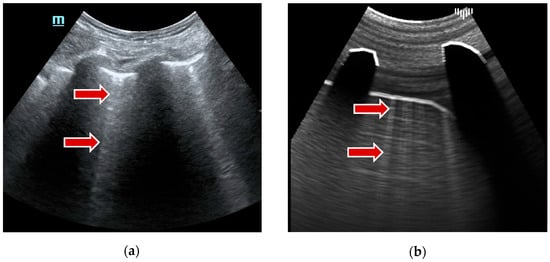

• Shadows are dark areas that occur when ultrasound waves are blocked or absorbed by dense structures, such as ribs or air-filled spaces (Figure 2). To simulate shadows, first, the cross-section image is rendered with Material attributes defined for each tissue. Then, a ray marching technique utilizes these values to compute shadows for each ray.

Figure 2. Ultrasound shadows example: (a) real examination; (b) the LUS simulation.